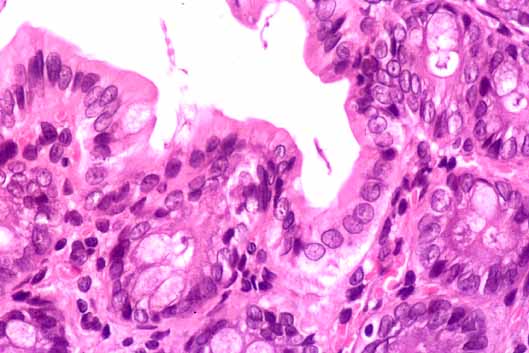

fig. 4

Figura 4.- Colon. Mucosa colónica con abundantes células caliciformes en las glándulas. Lamina propia sin particularidades. (x200)